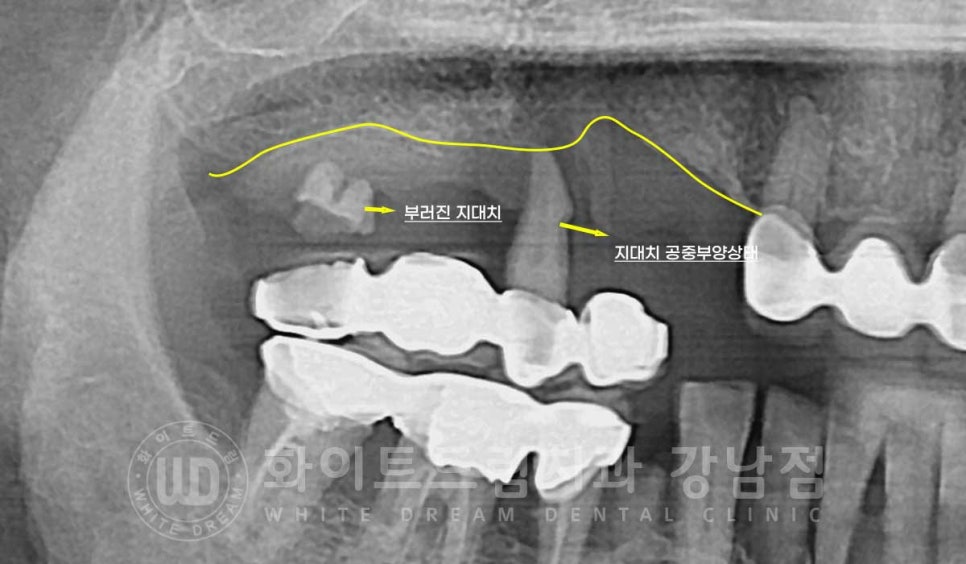

특히 10번대 브릿지의 상태가

구강 검진 시 기구로 살짝 건드리니 브릿지가 빠져버릴 정도로

상태가 정말 좋지 못했답니다.

브릿지 지대치 하나는 부러진 상태이고, 남은 지대치가 겨우 버티고 있는 상태였는데

검진시 기구로 살짝 건드리니 지대치가 자연 발거되버렸답니다.